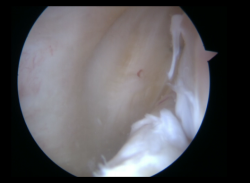

Aunque no se aprecien signos de inestabilidad meniscal desde una visión anterior, se realiza de forma sistemática una exploración del segmento posterior. Se realiza sistemáticamente una exploración visual del compartimento PM a través de la escotadura intercondílea, con flexión de rodilla de 90°. El artroscopio es introducido por el portal AL en el triángulo formado por el cóndilo medial, el ligamento cruzado posterior y la espina tibial. Tras introducir el artroscopio en este espacio, podemos avanzarlo hacia posterior sobre el borde del cóndilo, realizando un valgo forzado primero en flexión y luego en extensión. La rotación interna de la tibia puede ayudarnos en la visualización. Este gesto subluxa el platillo tibial posterior y produce una traslación posterior del tercio medio del platillo tibial. Con esta maniobra se pueden visualizar dos tercios de las lesiones periféricas que vayan desde el segmento posterior hasta el segmento medio. En caso de desgarros del segmento posterior, se realiza un portal PM (Figura 2). Mediante transluminación, el cirujano puede observar las estructuras vasculares y nerviosas de la zona para realizar el portal con seguridad. El punto de introducción de la aguja se sitúa proximal a los isquiotibiales, 1 cm posterior a la interlínea articular femorotibial medial. La rodilla se flexiona a 90° para evitar daños en el paquete poplíteo. La aguja se introduce de fuera a dentro en la dirección de la lesión.

Figura 2. Visión artroscópica a través del intercóndilo de la creación del portal posteromedial.